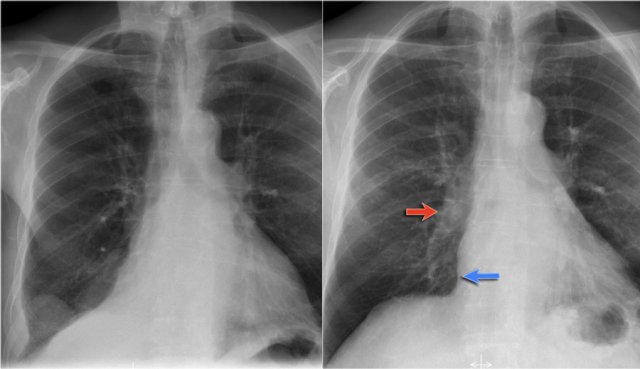

Diaphragm

The contours of the left and right diaphragm should be visible.

The right diaphragm should be visible all the way to the anterior chest wall (red arrow).

Actually we see the interface between the air in the lungs and the soft tissue structures in the abdomen.

The left diaphragm can only be seen to a point where it borders the heart (blue arrow).

At that point the interface is lost, since the heart has the same density as the structures below the diaphragm.